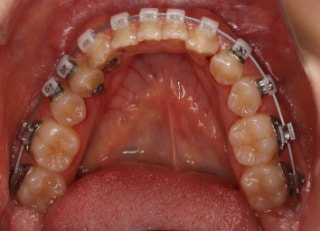

治療後(2年11ヶ月後)

治療開始から25ヶ月後